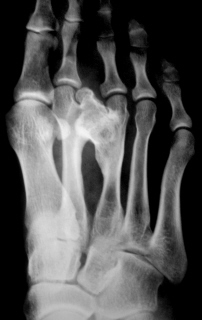

Иллюстрации 3 и 4 -  определяется тень дополнительного объёмного образования костной плотности, исходящая из дистальной ½ 3 плюсневой кости, растущее  и оказывающее компрессию на 2 плюсневую кость. В дистальном отделе 3 плюсневой кости определяется её уплотнение, утолщение и деформация. Расстояние между 2 и 3 плюсневыми костями увеличено, определяется некоторое расширение щели между основаниями 2 и 3 плюсневыми костями и между клиновидными костями. Определяется сужение суставной щели (по всей видимости компенсаторное) между латеральной клиновидной и кубовидной костями. По наружному контуру 2 плюсневой кости определяется умеренно выраженный периостоз, галюс вальгус, ротация проксимальной фаланги 1 пальца.

При исследовании структуры патологического образования с увеличением (иллюстрации 5 и 6) - объёмное образование состоит преимущественно из губчатой костной ткани, с хорошо выраженным кортикальным слоем, с чёткими контурами, местами определяются мелкие кистозные компоненты, местами мелкие участки остеосклероза. Участок периостоза по медиальному контуру патологического образования.